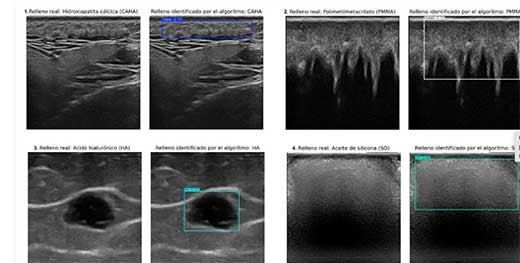

Este algoritmo es capaz de identificar y discriminar automáticamente, en imágenes ecográficas, cuatro tipos de rellenos cosméticos: hidroxiapatita cálcica, ácido hialurónico, polimetilmetacrilato y aceite de silicona.

Para entrenar al sistema, se utilizaron equipos ecográficos de diversa complejidad, desde unidades portátiles de pequeño tamaño hasta dispositivos de alta gama, garantizando así la adaptabilidad del sistema a diferentes entornos clínicos.